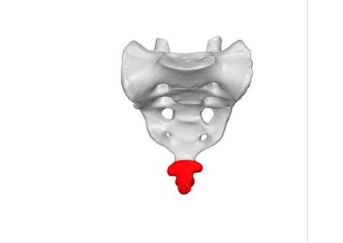

1-3

how many coccyx vertebra are fused together